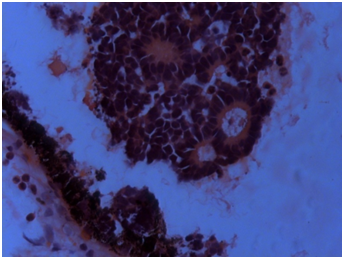

Transparent crystalline lens was separately examined and showed neovascularisation (Figure 2a-d). Enucleated eye ball showed tumour occupying almost entire vitreous cavity. Crystalline lens was seen separately which looked slight yellow and transparent. Three blood vessels were seen in the lens in the peripheral edge and were documented under background illumination. Portion of the lens was again dissected and haematoxyline & eosin (H&E) stain was carried out and it revealed regressed blood vessels in the cross section. Haematoxylin was put on the slide for 10-15 minutes followed by a wash in the running water, then one dip is made in 1% acid alcohol, slide was washed followed by addition of 0.4 % of ammonia for 1 minute. Third wash was made. Eosin was put on the slide for 1 minute and further washing is carried out. Xylene was added. Slide was dried and mounted for microscopic viewing. Study of the specimen in H&E stain showed normal cornea with focal iris neovascularisation. An endophytic tumor was seen in the vitreous cavity with numerous Flexner Wintersteiner (FW), Homer Wright (HW) and few new true rosettes4 (Figure 3). Zones of necrosis seen without any calcifications. Few vesicular cells along with basophilic undifferentiated cells and occasional apoptotic bodies were noted.5 Neovascularization of lens was also documented in H&E stained eyeball (Figure 4). Few pigment migrations were also noted. Exudations were seen in the section. Lateral calottes showed superficial involvement of the retinal pigment epithelium (RPE). The sclera was normal. Cut end of the optic nerve did not show tumor involvement. Immuno-Histochemisty (IHC) of the tumor was done for nueron specific enolase (NSE), glial fibrillary acidic protein (GFAP), p53, BCL2, transforming growth factor β (TGF-β). NSE and p53 were positive in the tumor sample and others were negative. GFAP, BCL2, TGF beta were negative in the lenticular portion of the eyeball as well as the adjoining basophilic tumour zone. Patient was reviewed by an oncologist at the regional cancer centre (Figure 5).

Figure 3 H&E stain showing a vessel on the posterior surface of the lens (X200).